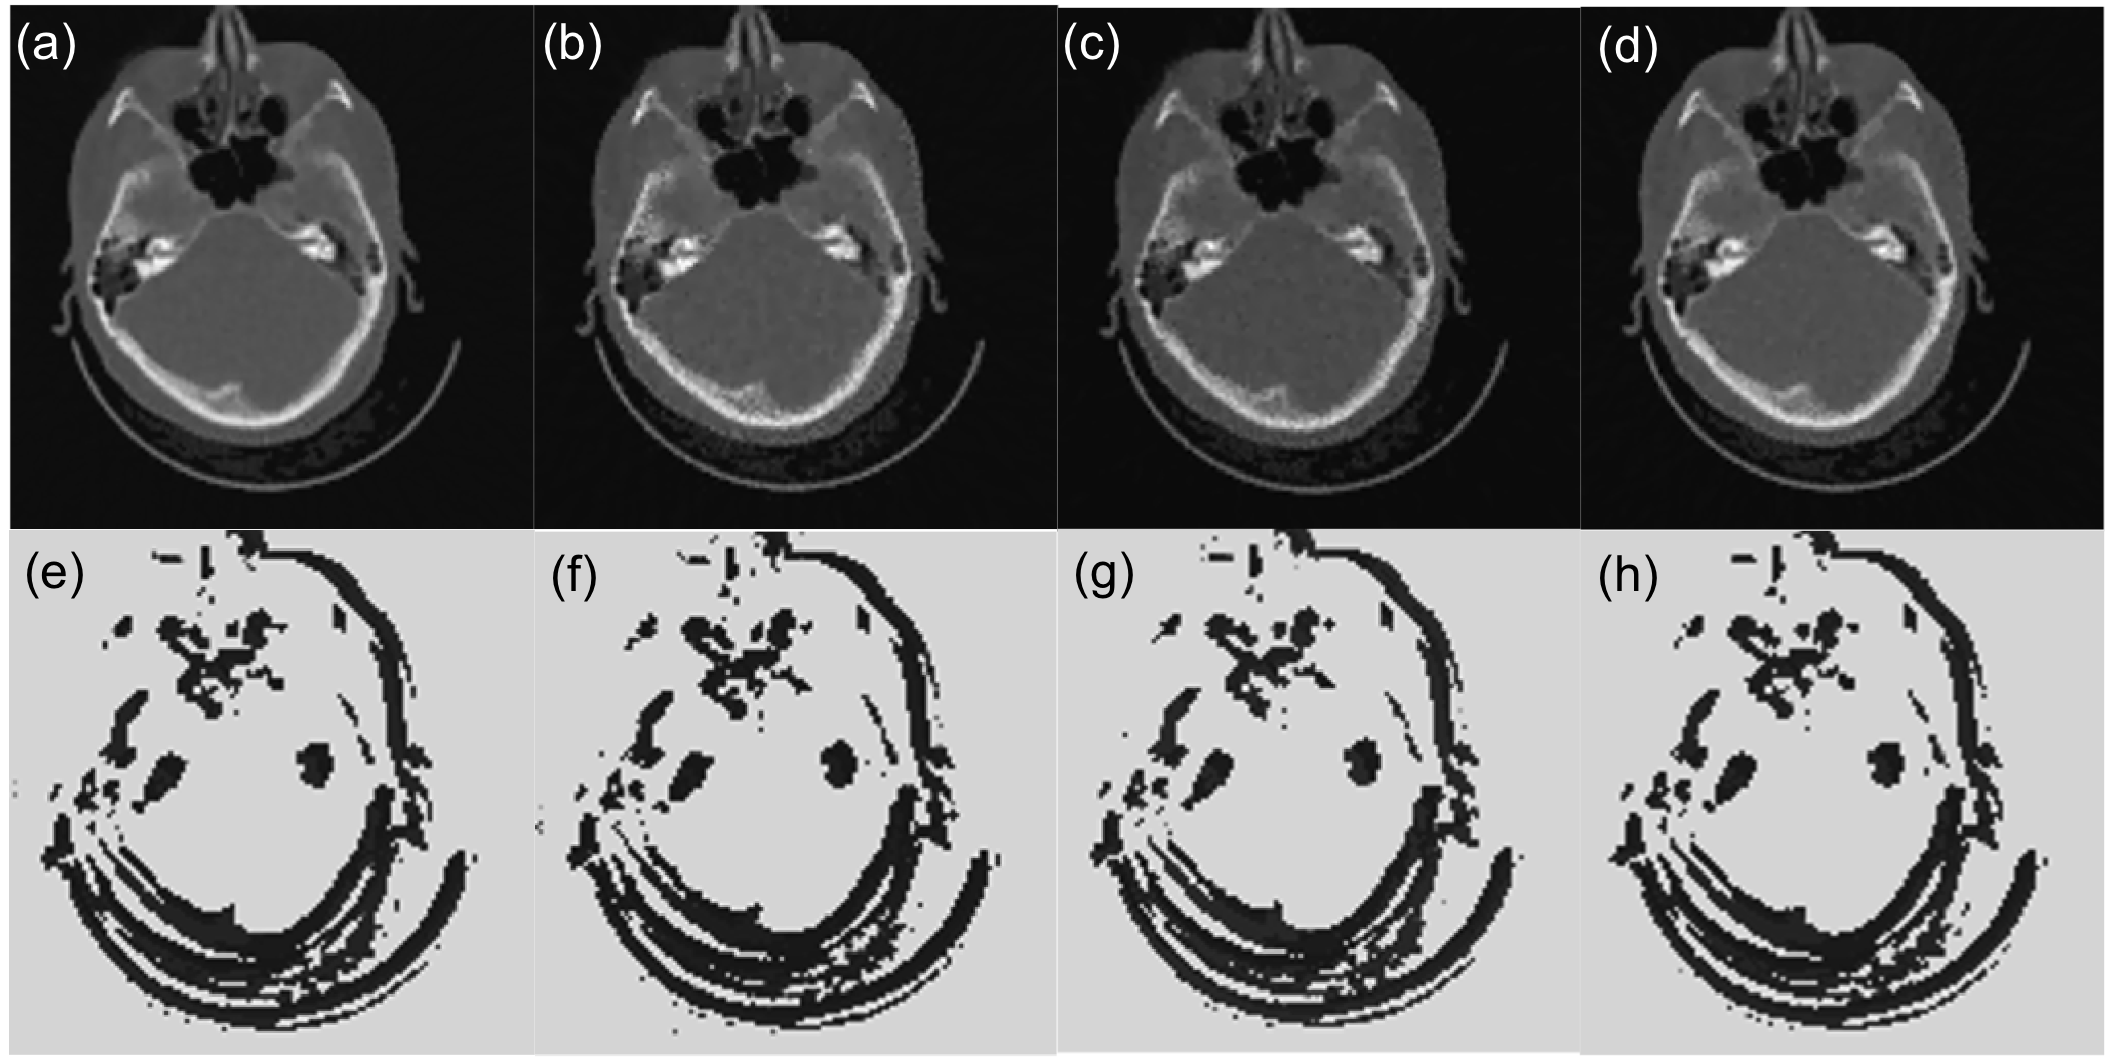

III-B3 Application to other cases

The PTPN determines the way of parameter tuning based on observed image patch. It is expected that the trained PTPN is also applicable to image reconstruction under settings that are different from that in training. To demonstrate this fact, we also applied PTPN to image reconstruction in cases with different number of projections, noise levels, and projection geometry. Fig. 8(a) and (b) are the same case as in Fig. 7 but with 2%percent22\% and 5%percent55\% noise in the projection data, different from the noise level of 3%percent33\% in training. Fig. 8(c) is the case with only 909090 projections. In Fig. 8(d) we change the isocenter-to-detector distance to 252525 cm. In all the cases, PTPN is able to adjust parameters to yield images with satisfactory quality. The resulting parameter maps in Fig. 8(e)-(h) are all similar to the ground truth shown in Fig. 7(f).

Refer to caption

Figure 8: (a)-(b) The results under tuned parameter for a case with 2%percent22\% and 5%percent55\% noise in the projection data. (c) The result with 909090 projections. (c) The result with isocenter-to-detector distance changed to 252525 cm. Figures in the bottom row are tuned parameter maps for corresponding figures in the top row.